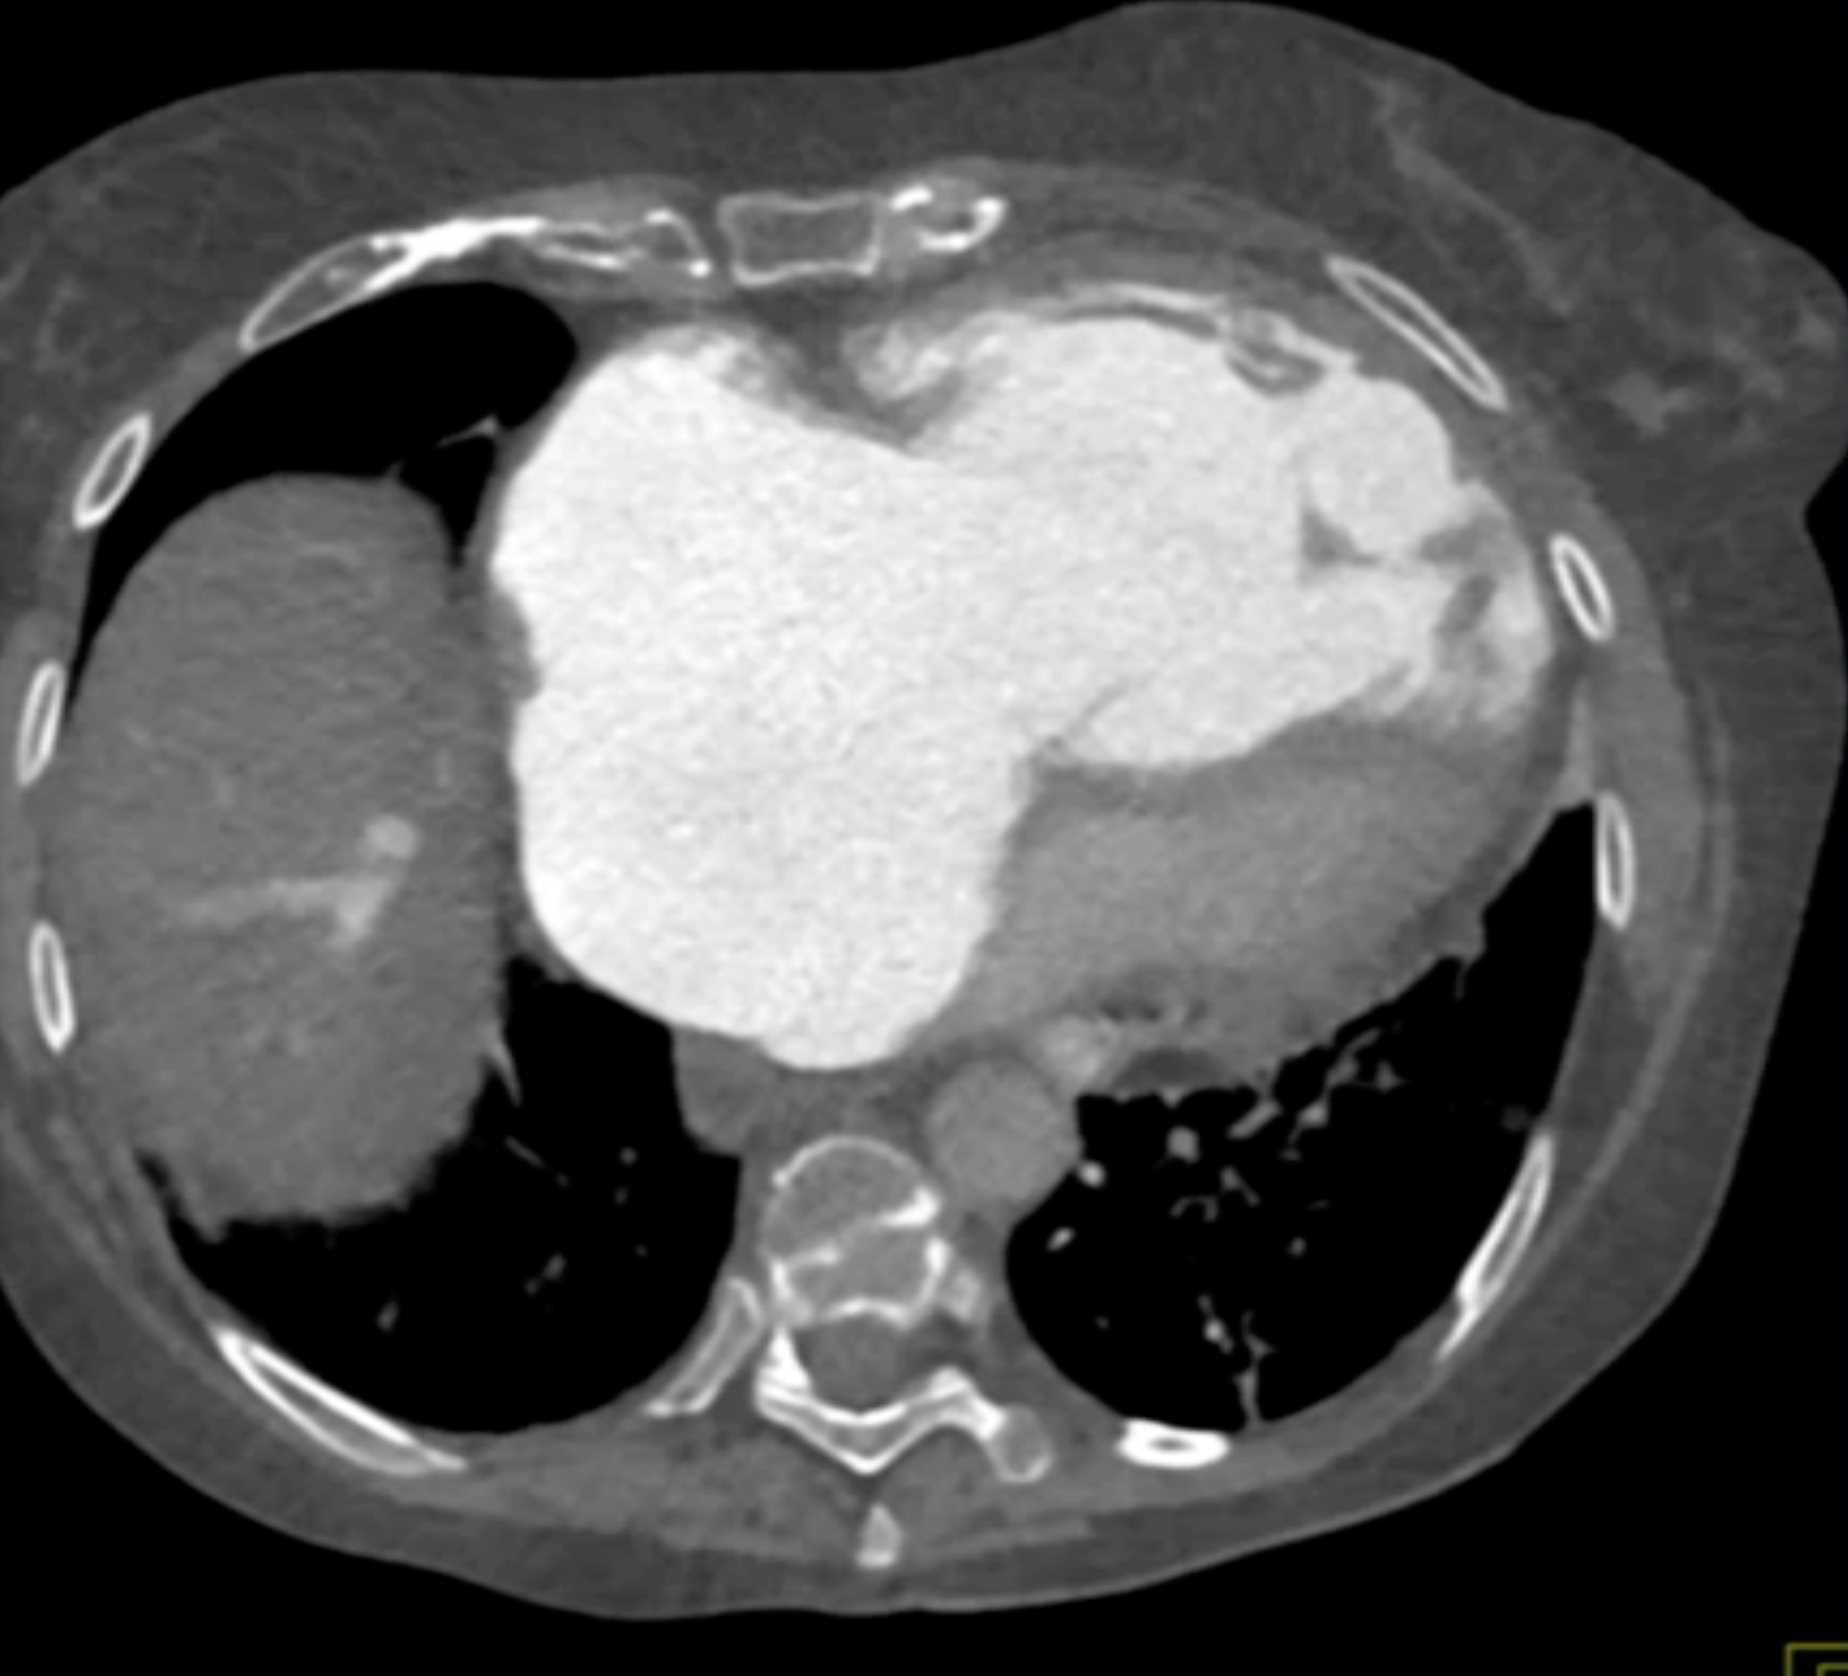

Fibrosing Mediastinitis involves the Pulmonary Artery and Vein